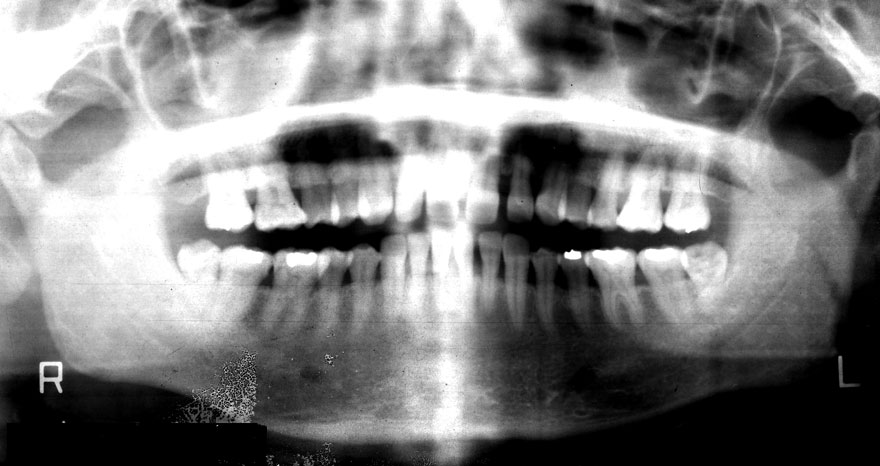

初診時 40歳 女性 平均歯槽骨喪失量:5.24mm

20年後 60歳

平均歯槽骨喪失量:5.79mm

21年間喪失量:-0.55mm

年間喪失速度:-0.027mm

(ケア頻度:1.23ヵ月ごと)